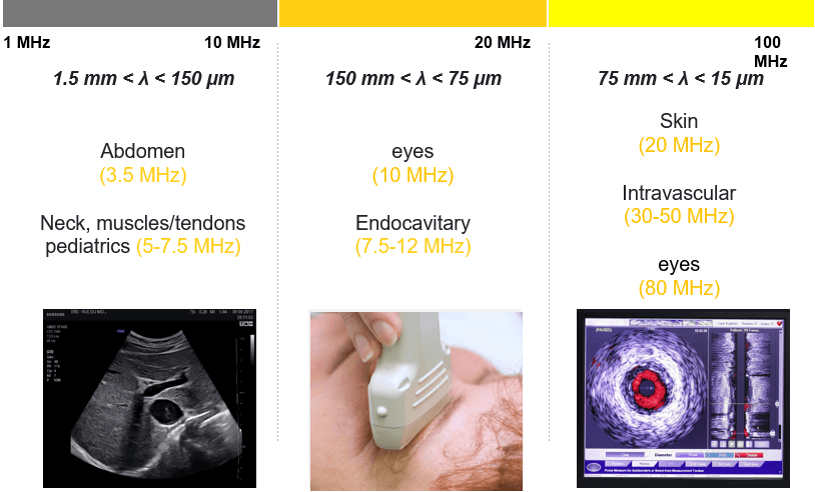

Acoustic Impedance

The acoustic impedance is a physical property of biological tissues. It describes the resistance that an ultrasound wave encounters as it passes through a tissue. It is important to know that the discontinuities in the acoustic impedance are responsible for the echoes on which the ultrasound imaging is based. The higher the difference in impedance, the greater the amount of reflection. The acoustic impedance depends on the density of the tissue(ρ in kg/m3) and the speed of the sound wave-wave (V in m/s); if the density of tissue increases, impedance increases. Similarly, if the speed of sound increases, then impedance also increases. Z = ρV

The bones have a high degree of reflection because their acoustic impedance is extremely high (7.8) compared to other tissues of the body. The air has a high degree of reflection because its acoustic impedance is extremely low (0.0004) compared to other tissues of the body. For this reason, it is important to apply a good quantity of conductive gel (a medium of acoustic coupling) on the transducer surface to eliminate any air pockets between the transducer and the skin surface.

Otherwise, most of the ultrasound waves will be reflected, limiting the penetration into the tissue. Highly dense tissues, such as bone or kidney stones, easily reflect echoes, and therefore, appear in white on an ultrasound image. Also, as in the intestine, the air reflects the echoes easily, so that the edge of the intestine appears in white on an ultrasound image. Thus, substances whose density differs significantly may appear in white on an ultrasound image. The acoustic properties of soft tissues are very similar to those of water. However, the acoustic property of the air is distinctly different; thus, the presence of air between the probe and the tissue of interest can deform and obscure the image. For this reason, a density of water, called coupling means, is used for the transmission of the ultrasound image. This coupling means is usually a sonographic jelly or lubricant that should be placed between the probe and the skin surface. At an air-tissue interface, 99% of the beam is reflected, and therefore, the application of this gel is highly important.

The greater the difference in acoustic impedance between two adjacent tissues, the more ultrasound energy will be reflected at the boundary. The acoustic shadow occurs when the sound wave meets a very dense structure. Almost all the sound is reflected, resulting in an acoustic shadow. Shading can occur due to intense reflectors such as calcification, air, or bone.

Reflection / Transmission

The Reflection of a sound wave occurs when the wave passes between two tissues of different acoustic speeds and a fraction of the wave ‘bounces’ back. Sound waves that are reflected directly to the transducer will lead to the vibration of the crystals, thus causing an electrical signal and creating the desired image. The equations of transmission and reflection of the ultrasonic intensity are independent of the frequency. Therefore, changing the transducer frequency does not change the transmitted or reflected intensity fraction at an interface. The three beams have the same direction.